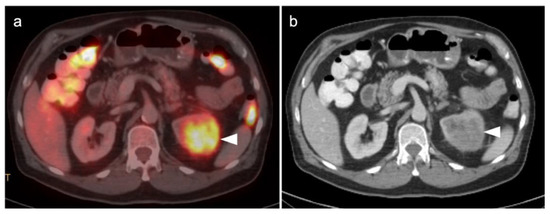

3.2. Urothelial Carcinoma

3.3. Primary Testicular Cancer